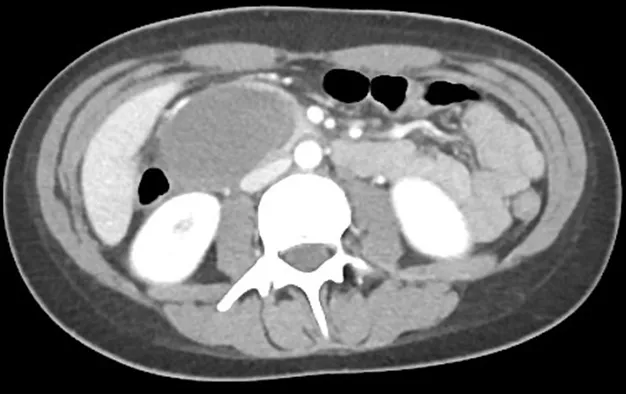

건강한 28세 여성이 자전거 사고 후 우측 상복부 통증을 호소하며 병원에 도착했다. 우측 상복부에 멍이 들어 있었고, 혈액 검사 결과는 정상 범위였다. 사고 후 사흘째, 환자는 담즙성 구토를 시작하여 상부 위장관 조영술과 복부 CT를 실시하였다. 적절한 치료방법은 무엇인가?

• 복부 컴퓨터 단층촬영 상 관찰되는 십이지장 부위의 intermediate density mass가 현재 폐색의 원인이다.

• 기저질환 없는 젊은 환자의 외상력과 우상복부 멍이 있는 점을 고려했을 때 외상으로 인한 십이지장 혈종이 발생하며 기계적 장폐색 (mechanical ileus)이 발생했다고 진단할 수 있다.